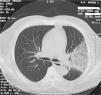

ResultsThere was no statistical difference between the age range of the two groups (53.8±18.2 in mild disease group versus 40.78±10.4 in severe group, p>0.058), and the predominant radiological findings in the patients at presentation were unilateral or bilateral multifocal ground glass opacities (twenty-three patients) (84.5%) (Fig. 1).

A 40-year-old man with influenza A (H1N1) virus pneumonia and severe respiratory failure (paO2/FIO2 at admission 180) who underwent non-invasive mechanical ventilation: chest computed tomography demonstrates patchy bilateral interstitial infiltrates and peripheral focal ground-glass opacities in the middle and lower lung zones.